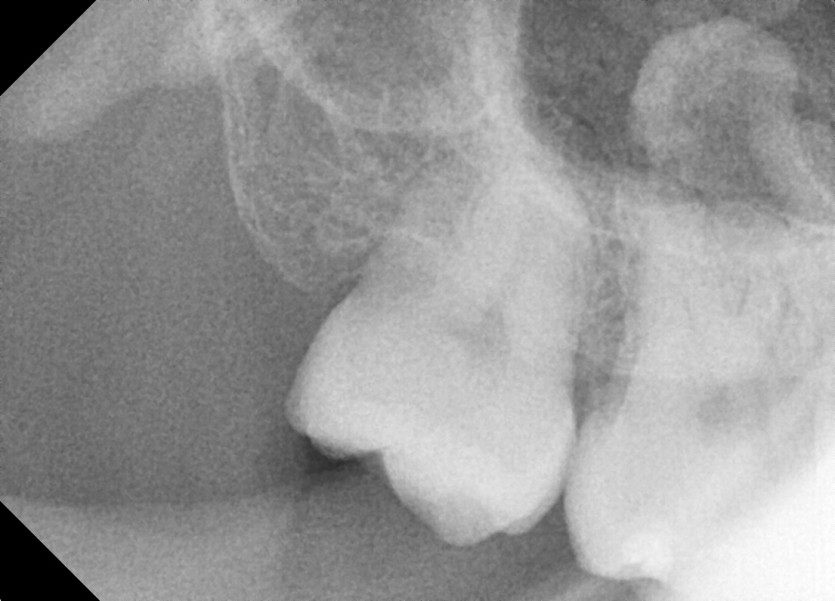

#18,48 사랑니 발치

구강 외과 전문의가 당일 발치했습니다.